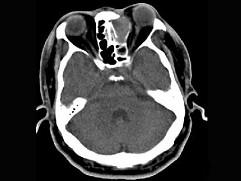

男,34岁,头痛、头晕3个月余,CT检查如图,最可能诊断为 ( )A、筛窦乳头状瘤B、筛窦黏液囊肿C、筛窦炎D、筛窦息肉E、筛窦癌

问题 男,34岁,头痛、头晕3个月余,CT检查如图,最可能诊断为 ( )

选项 A、筛窦乳头状瘤 B、筛窦黏液囊肿 C、筛窦炎 D、筛窦息肉 E、筛窦癌

答案 B